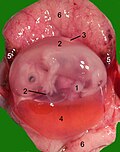

maternica s mačjim fetusom u sredini gestacije: 1 pupak, 2 amnion, 3 alantois, 4 žumanjčana vreća, 5 rubni podljev krvi, 6 majčin dio posteljice (endometrij)